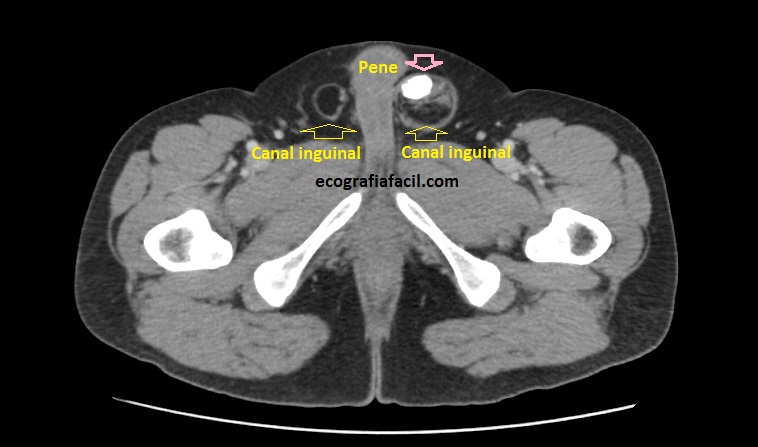

La anatomía ecográfica no deja lugar a dudas de la localización llegando muy cerca del testículo, ocupando el canal inguinal.

La lesión era bastante grande , ocupaba como ves en la imagen una parte importe del canal inguinal también en la imagen 7.

Se completa estudio con Ct ante las características de la lesión y la imagen que tenemos, muy llamativa, refrenda la presencia de una lesión en el canal inguinal que posee una gran calcificación.  En el CT se objetiva, imagen 7, una afectación ligeramente mayor a la estimada en el estudio ecográfico. La sospecha para la radióloga fue de lesión primaria de cordón inguinal compatible con Liposarcoma, a tenor de todos lo hallazgos en las dos pruebas, basándose principalmente en la heterogenicidad de la imagen, la calcificación y el comportamiento no compatible con hernia inguinal ni con la semiología típica del lipoma.